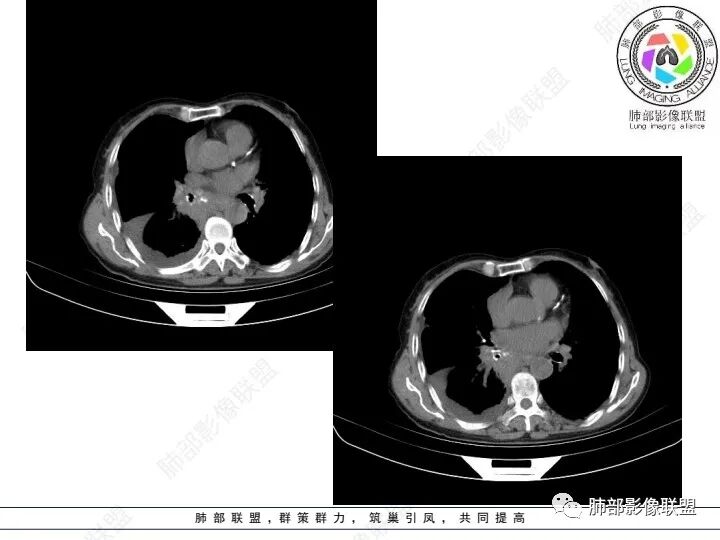

老年女性,肺气肿背景。腹痛、便血入院。右肺下叶脊柱旁软组织肿块,强化不均匀,中心有坏死,纵隔及双侧肺门多发肿大淋巴结、有融合,右下支气管周围为主,包绕支气管生长,且管壁增厚伴环形钙化、狭窄,增强后有环形强化。右侧胸膜见结节灶,增强后明显强化;右侧胸腔积液。考虑:右下肺恶性肿瘤伴纵隔、肺门多发肿大淋巴结,胸膜转移,低分化腺癌?Ca125明显升高,老年女性 是否有妇科恶性肿瘤?黏液腺癌 肺内、纵隔转移?

右肺下叶类圆形软组织密度影,纵隔及肺门多发肿大淋巴结、有融合,右下肺支气管壁增厚伴环形钙化、狭窄,右侧胸膜见结节灶,增强后均匀明显强化;右侧胸腔积液。考虑:右肺下叶肿瘤伴纵隔肺门、胸膜转移,考虑腺癌可能。

女,69,腹痛、便血4小时。CA125增高。胸部CT:肺气肿背景。右下叶不规则肿块影,处于外周气肿带与正常肺交界区,强化不均匀,中心有坏死;纵隔及肺门多发肿大淋巴结、融合,包绕支气管,部分钙化、环形强化;右下支气管周围管壁增厚伴环形钙化、狭窄。右侧胸膜多发结节灶,增强后明显强化,右侧胸腔积液。考虑恶性,右下肺腺Ca多发转移?转移瘤?鉴别TB、IgG4等。

3、胸部增强CT示右肺下叶脊柱旁不规则软组织肿块,侵及壁层胸膜外,密度不均匀,不均匀强化,中心低密区可疑坏死,右侧胸腔积液、胸膜结节影或结节样增厚,增强扫描可见强化,右侧肺门及纵隔内可见淋巴结肿大、融合,右侧中尖段支气管及右肺下叶支气管受侵,管腔狭窄。